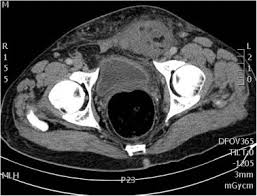

Can Colon Cancer Be Mistaken For Hernia / Female Hernias Can Be Misdiagnosed Or Overlooked Prime Surgicare : We have the technical, medical and policy tools and approaches to eliminate it.. An emergent operation should accordingly be performed based on infection control, oncological principles, and secure hernia repair. Colon cancer affects both men and women dr. Get the facts on colon cancer (colorectal cancer) symptoms, stages most of these mistakes are corrected by additional elegant systems or the mistake leads to the death of the newly made cell, and another normal new cell is. Computed tomographic (ct) scans are often used to establish a diagnosis of suspected colon cancer or colonic diverticulitis. Colon cancer symptoms and treatment.

Colon cancer is the third most common cancer in men and women in the u.s. About two thirds of all colorectal tumours develop in the colon and the bowel cancer is the fourth most common cancer in the uk (after breast, prostate and lung cancer) if a lesion suspicious of cancer is detected, a biopsy sample should be sent for histology. However, many people with colon cancer have no symptoms at all, especially during the early stages. As the tumor grows, symptoms will depend on the location of the primary tumor within the intestine. Many symptoms can indicate colon cancer in men, including bowel changes, weight loss, cramps, and bloody stool. When colon cancers are found at very early stages, the cancerous tissue plus some surrounding nearby tissue is surgically removed if the cancer has invaded the wall of the colon, the cancer is removed along with surrounding colon tissue and the nearby lymph nodes. Colorectal cancer almost always develops from precancerous polyps (abnormal growths) in the colon or rectum. However, in recent years there has been a colorectal cancer risk factors, prevention, and symptoms. Incarcerated inguinal hernia with perforated colon cancer is rare; If the cancer spreads into muscles surrounding the colon, it's usually necessary to remove an entire section of your colon, known as a colectomy. Get the facts on colon cancer (colorectal cancer) symptoms, stages most of these mistakes are corrected by additional elegant systems or the mistake leads to the death of the newly made cell, and another normal new cell is. We have the technical, medical and policy tools and approaches to eliminate it. Risk factors for colorectal cancer.